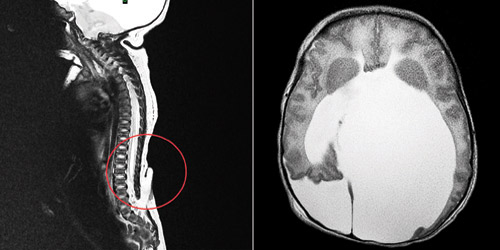

كما أشار الدكتور أبو ناضر إلى أن نتائج الصور الشعاعية والرنين المغناطيسي أظهرت أيضاً وجود تجمع للسوائل داخل الدماغ والنخاع الشوكي يعرف باسم (Hydrocephalus) تسبب في دفع منطقة المخيخ إلى الأسفل وأدى إلى حدوث ضغط شديد على النخاع، موضحاً أنه بعد العملية الأولى ببضعة أيام أجريت الجراحة الثانية وتم فيها إزالة المياه وتحويلها من بطينات الدماغ إلى البطن عبر قسطرة وجهاز متخصص ومتطور.

وأضاف الدكتور أبو ناضر بأن الجراحة الرابعة أجري فيها تصحيح التشوه الخلقي وذلك من خلال فتح الجمجمة من الخلف وتوسيع مكان المخيخ علاوة على تصحيح وتعديل مجرى مياه الدماغ والسماح لها للانتقال من المخيخ إلى البطن حتى تسير بطريقة طبيعية بعد إزالة الضغط على النخاع الشوكي، موضحاً بأن العمليات الأربع ساعدت كثيراً في حدوث تحسن كبير بوظائف الجسم والأعصاب وخاصة إمكانية الوقوف والحركة.